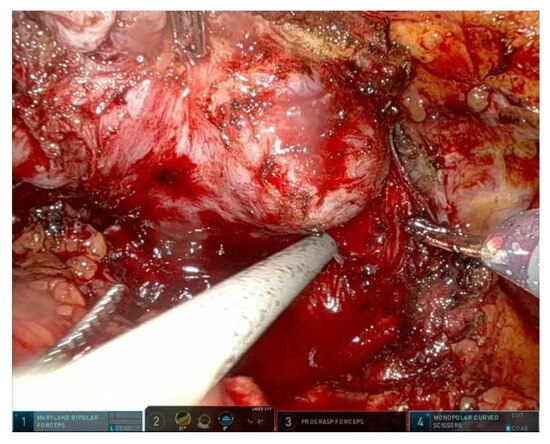

Figure 2. Clipless right prostate pedicle section and develop of right intrafascial plane. - Interfascial: partial preservation, balances functional and oncological outcomes; Figure 3 shows a frame during interfascial dissection;

Figure 3. Clipless left prostate pedicle section and beginning of left interfascial plane.